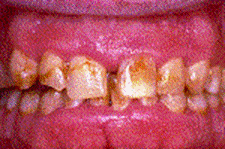

Gingivite

sângerare la periaj/sondare

gingie de culoare rosie, tumefiata, neteda, lucioasa, sensibila la palpare

halena

pungi parodontale false

ANUG

elefantiazis gingival